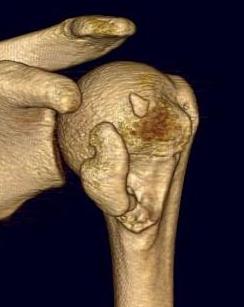

Four part

Avascular necrosis (AVN)

In most fractures, arcuate artery is disrupted, but head survives

- posterior circumflex artery is sufficient

- risk increases with amount of displacement

- 4 part fracture 30%

- 3 part fracture 15%